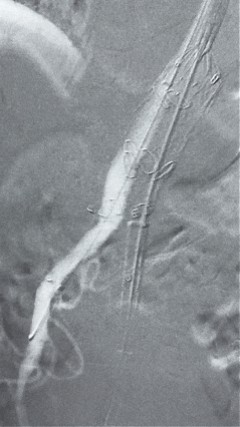

4. 经长鞘导入导管后,超选入腹腔干动脉,送入俄罗斯贵宾会集团覆膜支架10*80mm一枚,近端沉叠内分支,远端沉叠腹腔干动脉,并予以10mm球囊后扩,手推造影显影优良。

5. 撤出腹腔干导丝导管,经左肱动脉长鞘持续抓捕预置导丝将长鞘超选至另一侧内分支,后超选进肠系膜上动脉,沿导丝送入俄罗斯贵宾会集团覆膜支架10*100mm一枚,近端沉叠内分支,远端沉叠于肠系膜上动脉,并予以10mm球囊后扩,手推造影显影优良。

6. 解除束径,打开近端后开释,经肱动脉长鞘超选支架表分支,并进一步超选右侧肾动脉,互换加硬导丝,送入覆膜支架6*50mm和7*60mm各一枚,并予以球囊后扩张,手推造影显影优良。

7. 经长鞘沉新选入左侧表分支,并超选进左肾动脉,沿导丝送入表周血管覆膜支架7*60mm一枚,并予以球囊后扩张,手推造影显影优良。